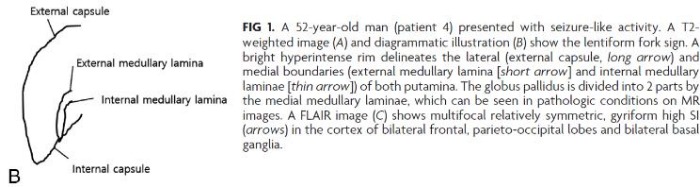

Визуализация мозга чаще всего выявляет его атрофию и увеличение желудочков. Тем не менее иногда, в ограниченном числе случаев при МРТ головного мозга можно обнаружить специфические изменения в области базальных ганглиев, хотя подобные признаки могут сопровождать и метаболический ацидоз, и метаноловую интоксикацию. Изменения, лучше всего заметные в режимах Т2-WI/FLAIR, представляют собой гиперинтенсивные четко очерченные границы скорлупы (латерально — наружная капсула, медиально — внутренняя капсула, внутренняя и наружная мозговые пластинки) с обеих сторон и в целом по форме несколько напоминающие вилку. По сути это является отображением диффузного вазогенного отека базальных ганглиев из-за нарушения процессов ауторегуляции.

- Kim D. M., Lee I. H., Song C. J. Uremic encephalopathy: MR imaging findings and clinical correlation //American Journal of Neuroradiology. – 2016.